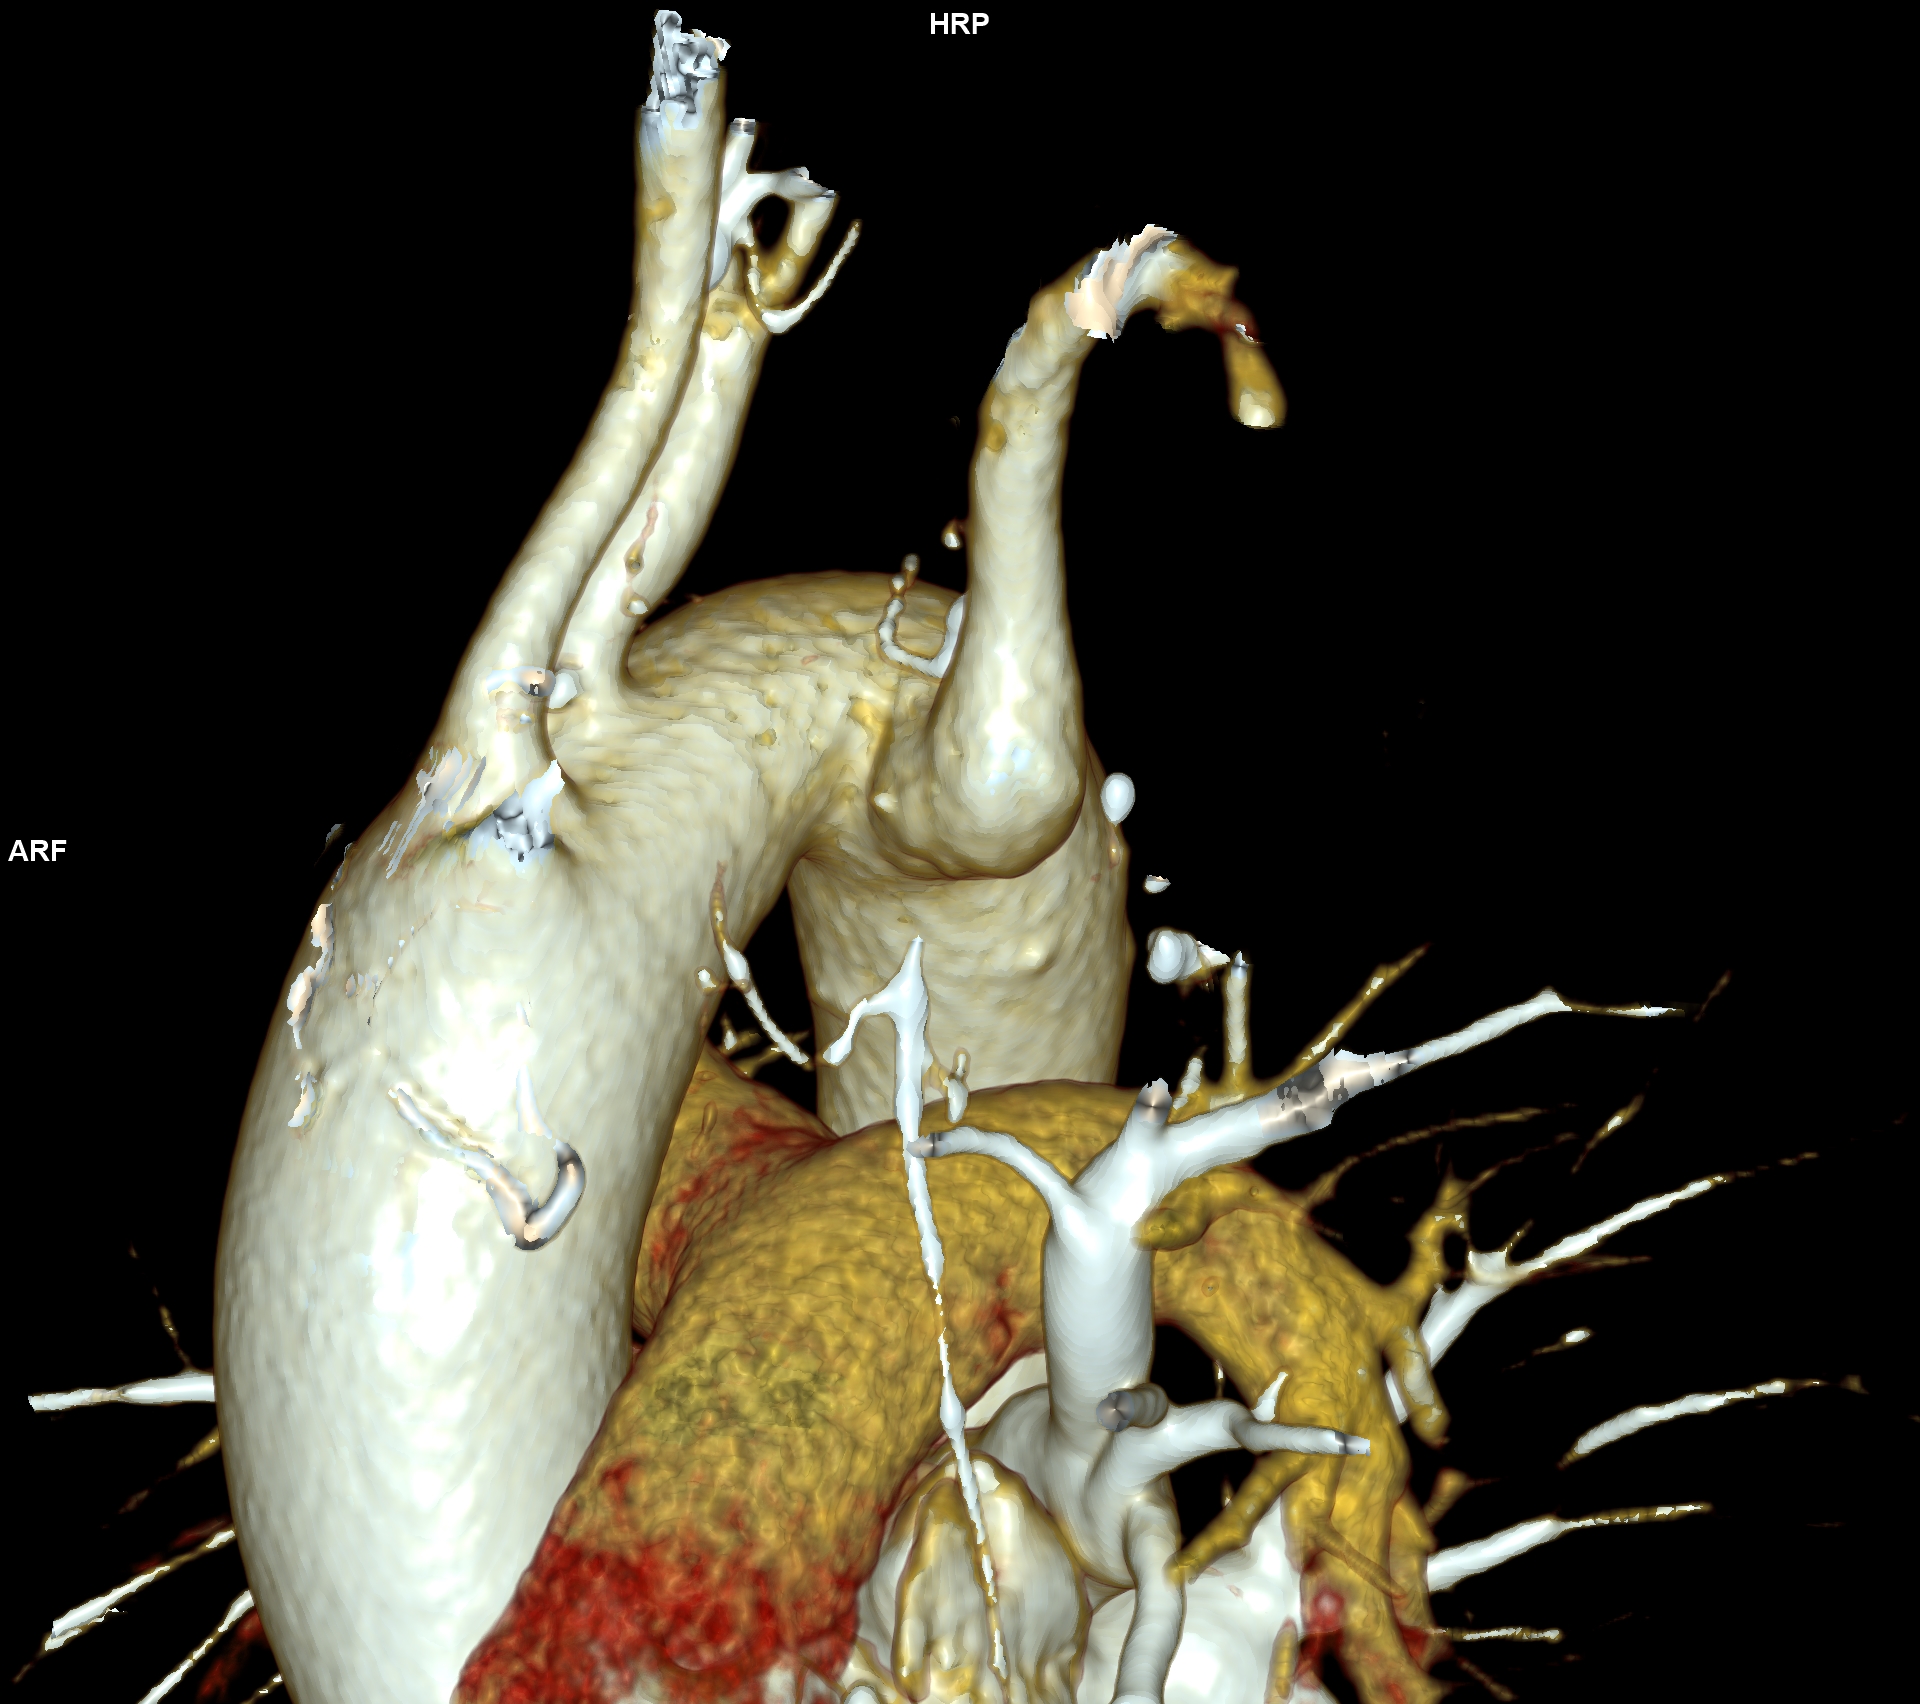

CAZ nr 57: Arc aortic de partea dreaptă si diverticul Kommerell

Figura 3, 4, 5: reconstrucție de volum 3D din achiziție angioCT toracică